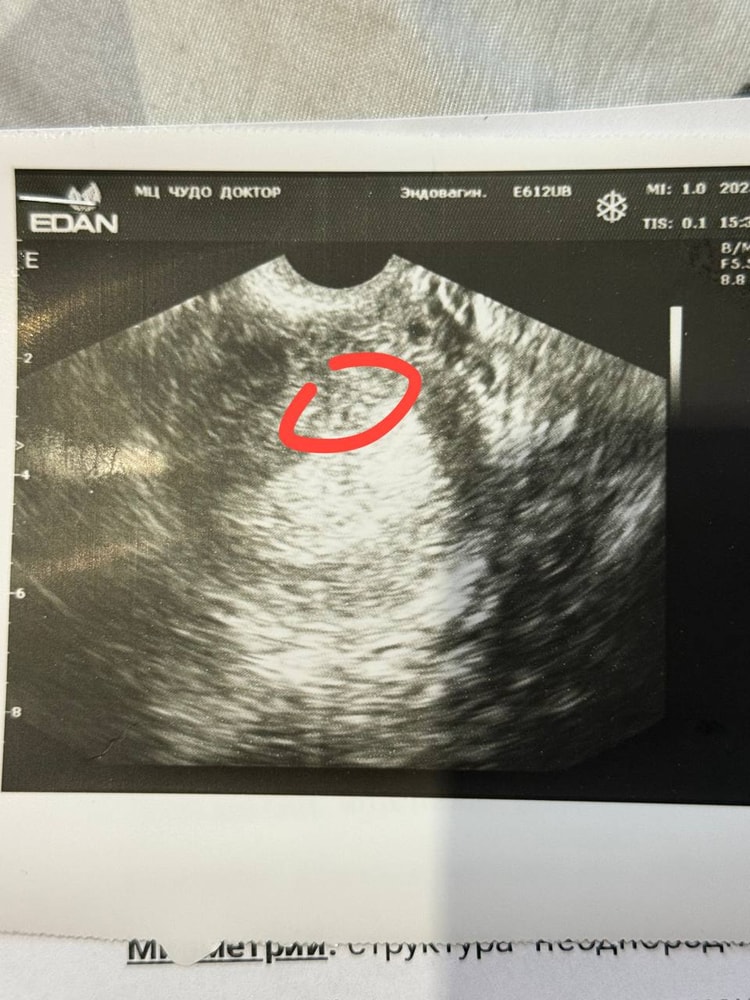

Со вкусом счастья , Изображение

Анастасия, так таких точечек в полости матки на данном узи снимке можно море выделить… сомнительно, но океееей) p.s. то, что вы выделили вообще далеко от образа пя..